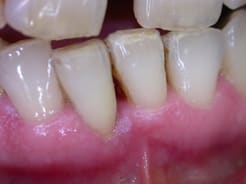

si ...alors la suite ....

cicatrisation à 6 mois

par contre je suis persuadé qu'il ne faut pas sonder pas irriguer plus qu'il ne faut surtout si comme dans le cas ou celui de Carole la composante occlusale prend le dessus sur la composante infectieuse .. Si abcès en urgence atb probabiliste de type metronidazole ...pas de tests . J'ai mis volontairement la sonde sur la photo pour montrer qu'à 6 mois seulement j'avais sondé pas avant.au niveau muqueux c'est cicatrisé mais au niveau osseux il faut encore 3 mois au moins